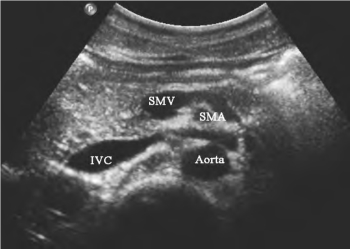

1.36.4四、腹腔大血管